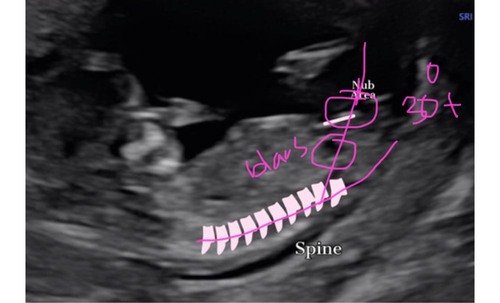

Pff goed verdienmodel zeg😅 Ik zou adhv de nub theorie ook meisje zeggen ma ...

Ik heb het via een ander bureau laten doen. De nub whisperer ofzo. Ik kreeg ook 99,5% zekerheid op een meisje en bij mij klopte het! Jouw nub lijkt me ook echt een meisje. De stand in combinatie met de positie van de blaas = 👧

Maar je ziet zelfs boven de nub iets zitten + de blaas is obviously van een jongen want staat erg laag. Wat dom dat ze dit gestuurd hebben 😂

Zo zou ik hem getekend hebben